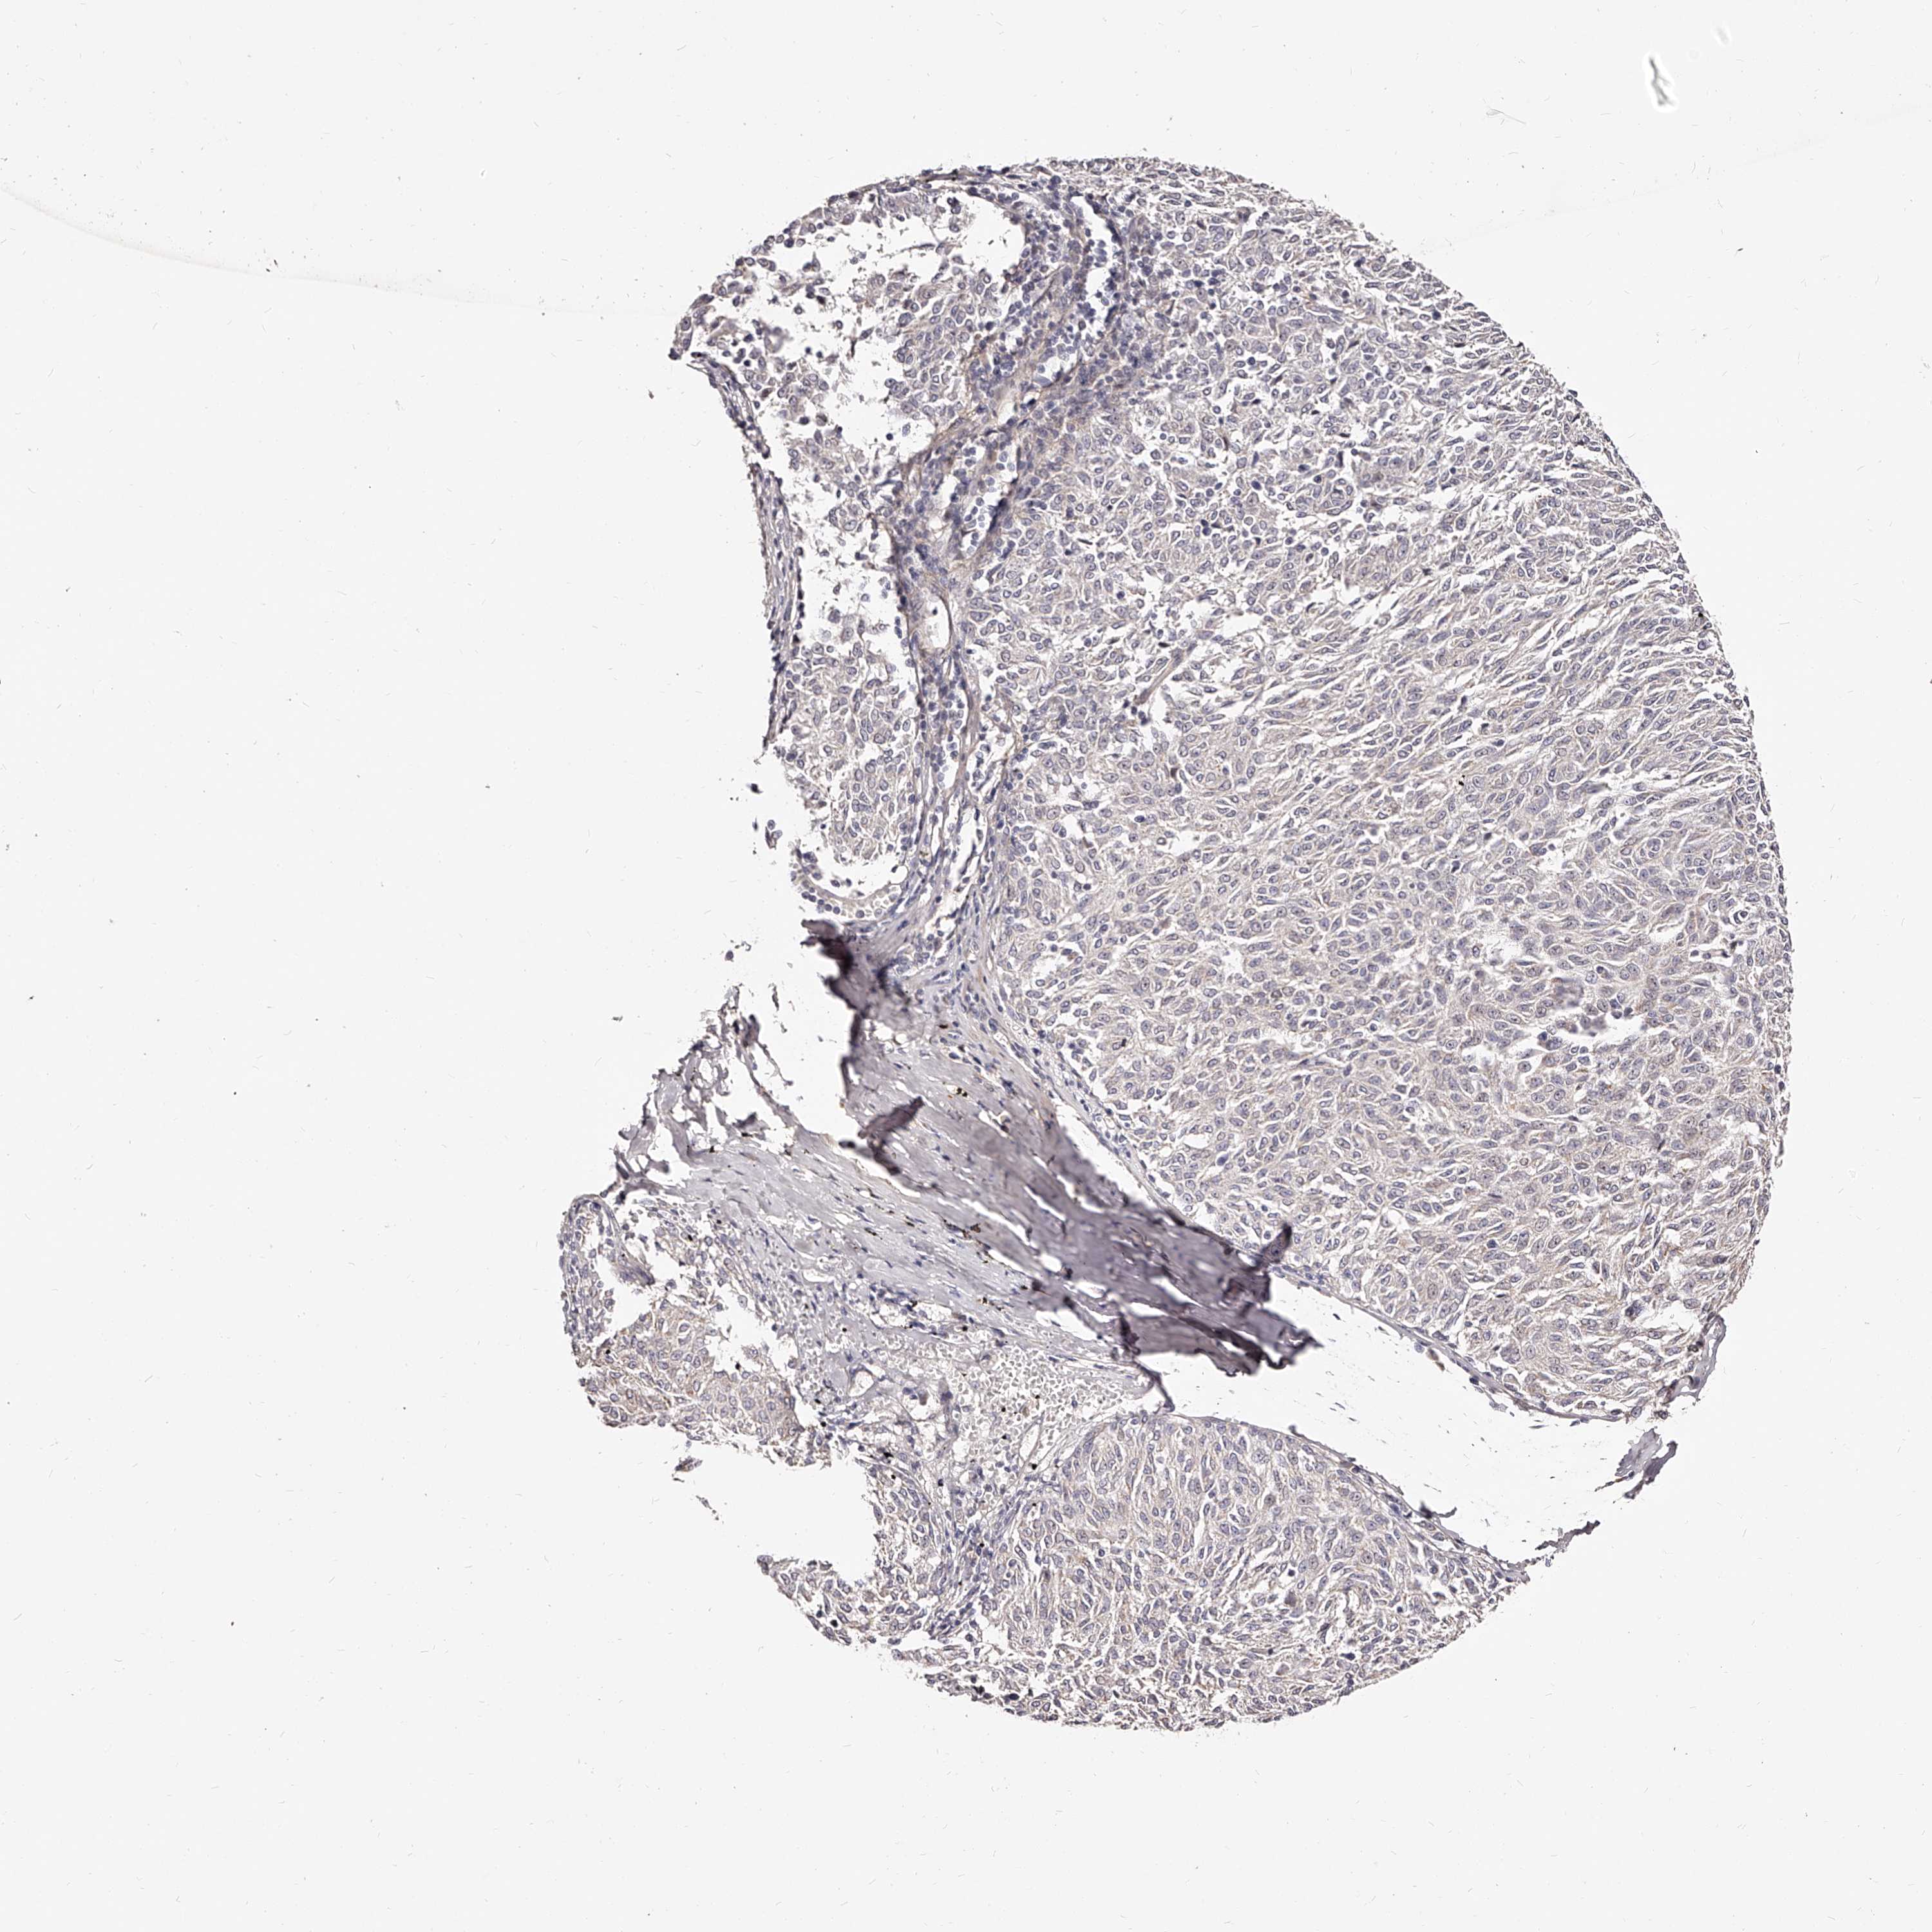

MELANOMA - Protein expressioni

A mouse-over function shows sample information and annotation data. Click on an image to view it in a full screen mode. Samples can be filtered based on level of antibody staining by selecting one or several of the following categories: high, medium, low and not detected. The assay and annotation is described here.

Note that samples used for immunohistochemistry by the Human Protein Atlas do not correspond to samples in the TCGA dataset.

Antibody stainingi

Antibody staining in the annotated cell types in the current human tissue is reported as not detected, low, medium, or high, based on conventional immunohistochemistry profiling in selected tissues. This score is based on the combination of the staining intensity and fraction of stained cells.

Each image is clickable and will lead to virtual microscopy that enables deeper exploration of all samples and also displays staining intensity scores, fraction scores and subcellular localization as well as patient and tissue information for each sample.

Antibody HPA024761

Antibody HPA029557

Staining

High

Medium

Low

Not detected

Intensity

Strong

Moderate

Weak

Negative

Quantity

>75%

75%-25%

<25%

None

Location

Nuclear

Cytoplasmic/membranous

Cytoplasmic/membranous,nuclear

Malignant melanoma, NOS